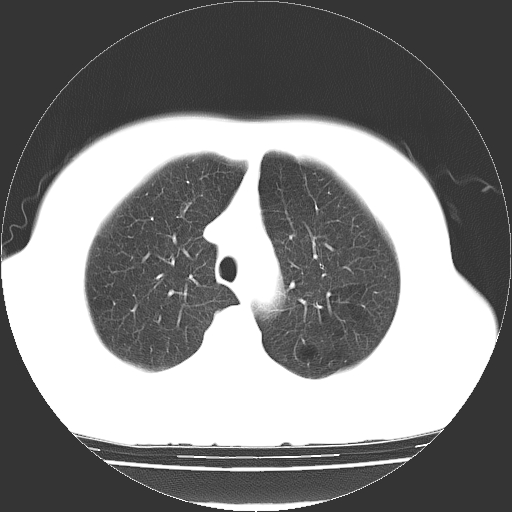

标题: CT13141:女,70岁,咳嗽、胸闷半个月。 [打印本页]

标题: CT13141:女,70岁,咳嗽、胸闷半个月。

女,70岁,咳嗽、胸闷半个月。纵隔窗未见异常,未上传。

小叶中心型肺气肿并多个肺大泡形成。

小叶中心型肺气肿并多个肺大泡形成

双肺肺气肿并多发肺大泡